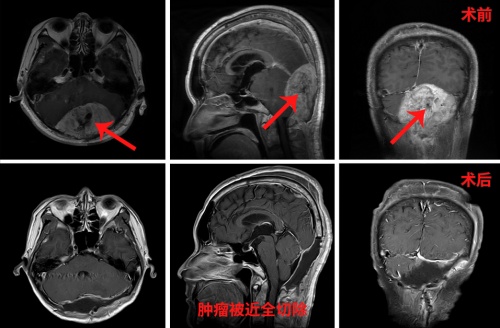

分站式复合手术切除鹅蛋般大小脑转移瘤 三博脑科让肾癌脑转移瘤患者蝶变重生

今年8月,刘东后脑勺突然头痛,呈阵发性刺痛,走路越不越不稳,食欲下降,人也越来越消瘦。家人陪同他到当地医院,经过脑CT检查,发现“小脑占位竟有8厘米,有鹅蛋般大小,同时伴有颅骨内外板破坏,脑积水。”

张宏伟教授仔细阅片后,发现颅内转移瘤过于巨大,达8厘米多,供血丰富,常规开颅手术切除肿瘤确实容易发生术中大出血,容易出现失血性过多而被迫中止手术的极端情况。不过患者病情严重,只有通过手术才能解决。张宏伟教授表示,可以采用分站式手术方案,先进行肿瘤血管的栓塞,然后再进行手术切除肿瘤,这样可以增加患者的生存机会。

随后,刘东被救护车紧急送到医院。入院后,张宏伟教授立即联合神经介入科主任刘加春等进行联合会诊。专家们决定实施分站式复合手术策略,一期手术先为患者行“全脑动脉造影术+富血运肿瘤供血栓塞术”,能有效减少手术切除过程中的出血量,且栓塞后可导致肿瘤缺血坏死,使之与正常脑组织分离,有利于完整切除,降低手术难度,增加手术***性。二期手术再全麻下行“脑转移瘤切除术”,解除风险。

既是性命相托,定当全力以赴。10月21日,经过详尽的手术方案和充足的手术预案后,刘东被推入了手术室,在全麻状态下,张宏伟教授团队为其实施了“后正中巨大脑转移瘤切除术”。

术中,张宏伟教授不急不躁,步步为营,极其耐心地一点点分离肿瘤界面,同时细心止血……分离肿瘤与硬膜、神经组织、血管后,最终将肿瘤近全切除。下午6时许,走出手术室的那一刻,张宏伟长长地舒了一口气,手术圆满成功,术中出血约650ml,患者安返ICU重症监护室进行监护。术后患者不久恢复清醒,自我感觉头脑较前更清醒,语音、语速恢复较好,各项功能正常。

经过观察,病人病情逐渐稳定,由ICU转回普通病区。张宏伟教授和主管医生每天都要数次查房,仔细为患者查体、调整治疗措施、定时给患者换药。刘东情况一天比一天好转,两天不到就可以自主饮食,头痛症状明显缓解,可以自主大口吃饭了,不到一周便已能正常行走,两周就顺利出院……